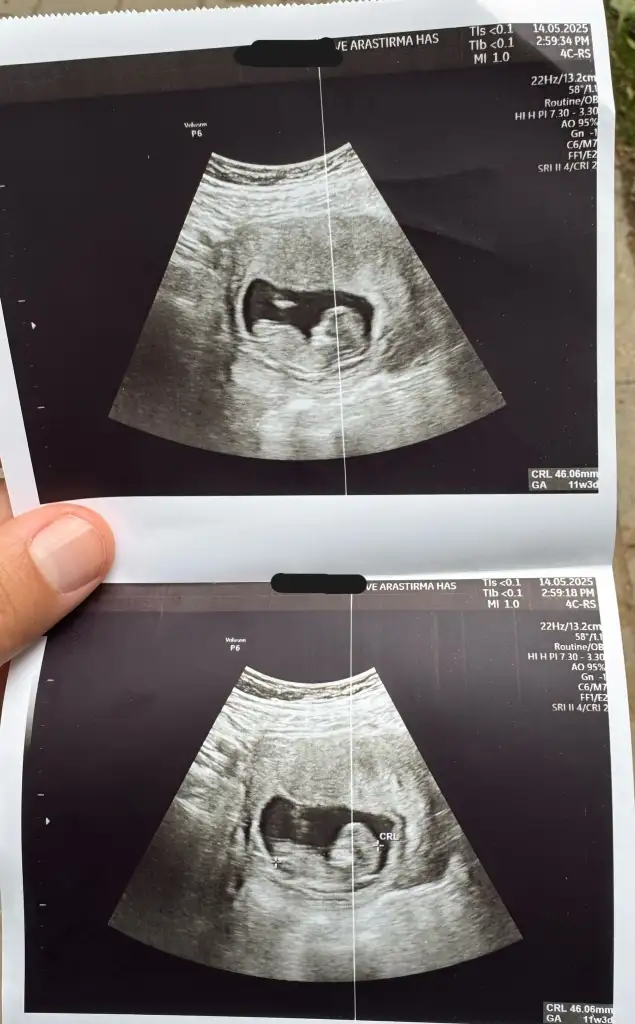

SATa göre 12 haftalıkKaç haftalık minik

Kız hissettimMerhabalar rica etsem bana da tahminde bulunabilirmisiniz 11+4 haftalık